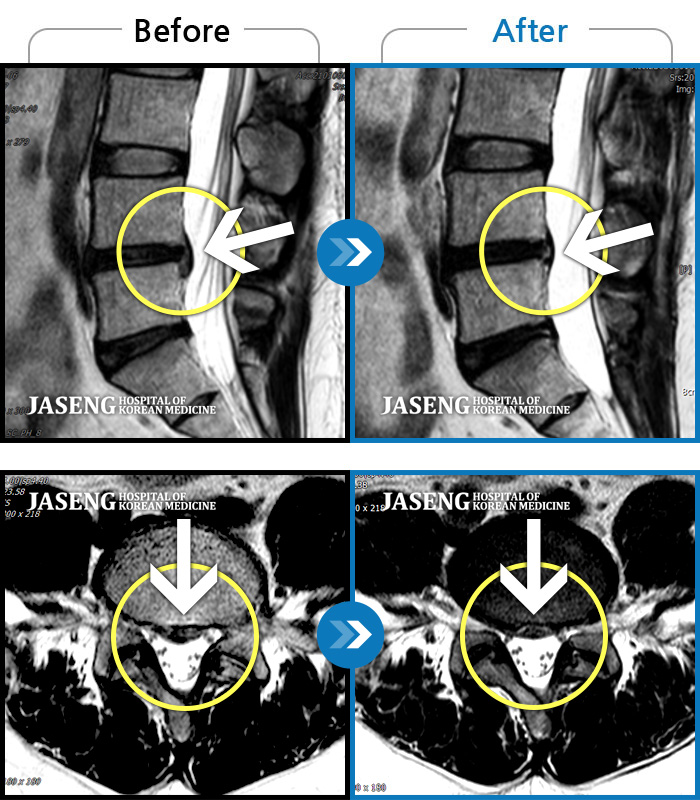

허리디스크

강남 · 강만호 원장

허리통증 및 왼쪽 다리 통증으로 운전이 불가능했습니다.

촬영시기

2023.10.16 ~ 2024.10.14

2024.10.23